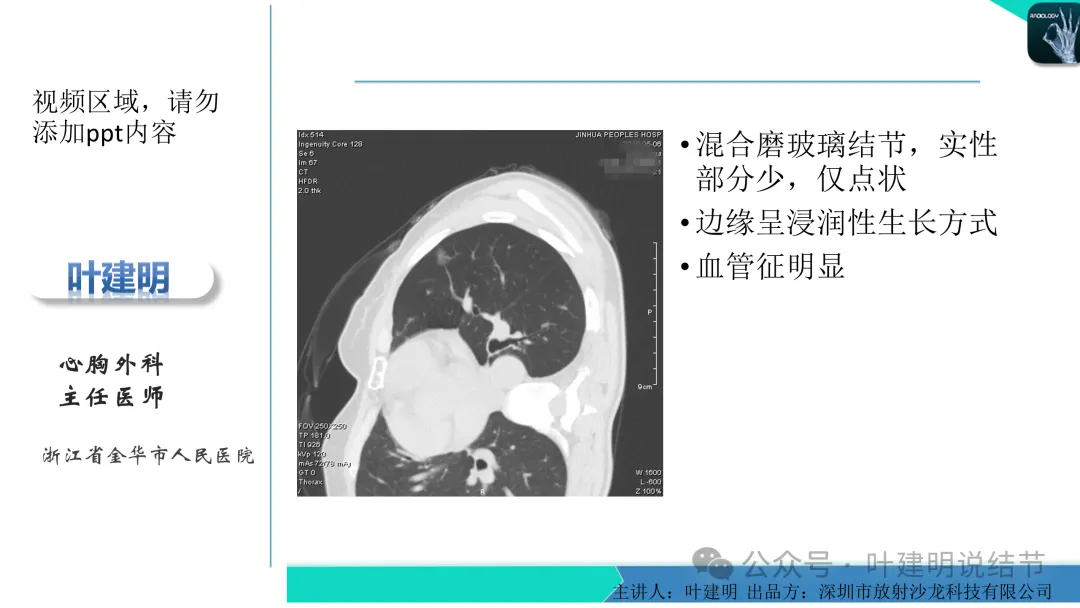

早在2020年时,我受邀在《放射沙龙》做过一个系列的精品课,当时专门总结分析过各类良恶性肺结节与肿块的影像特征,这是当时关于微浸润性腺癌影像特征的分析,今天看来仍基本不太需要改变,大家有兴趣的可以参考: